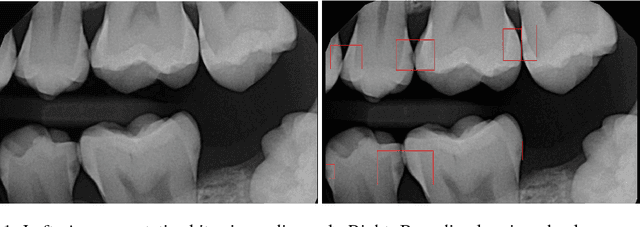

Abstract:We develop a Computer Aided Diagnosis (CAD) system, which enhances the performance of dentists in detecting wide range of dental caries. The CAD System achieves this by acting as a second opinion for the dentists with way higher sensitivity on the task of detecting cavities than the dentists themselves. We develop annotated dataset of more than 3000 bitewing radiographs and utilize it for developing a system for automated diagnosis of dental caries. Our system consists of a deep fully convolutional neural network (FCNN) consisting 100+ layers, which is trained to mark caries on bitewing radiographs. We have compared the performance of our proposed system with three certified dentists for marking dental caries. We exceed the average performance of the dentists in both recall (sensitivity) and F1-Score (agreement with truth) by a very large margin. Working example of our system is shown in Figure 1.